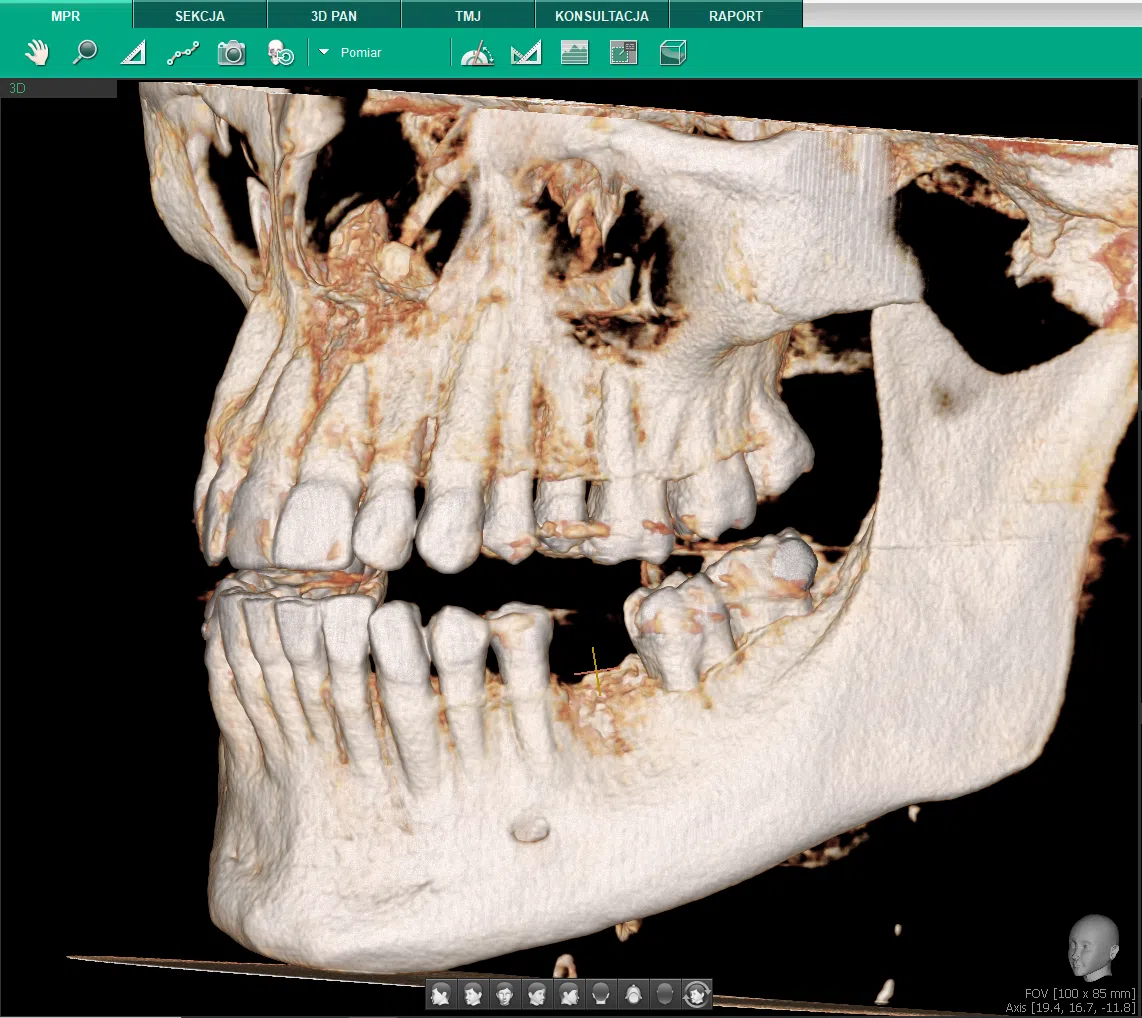

Gdy plan leczenia obejmuje wiele sektorów, obie szczęki jednocześnie lub łączy implantologię z diagnostyką ortodontyczną – badanie sektorowe nie wyczerpuje potrzeb diagnostycznych. Tomografia CBCT szczęki i żuchwy z dużym polem widzenia dostarcza w jednym obrocie gantry trójwymiarowy obraz całego kompleksu zębowo-szczękowego: uzębienia, wyrostków zębodołowych, dna obu zatok szczękowych, kanałów żuchwowych obustronnie i stawów skroniowo-żuchwowych. Jeden plik DICOM dla ortodonty, implanatologa i chirurga – bez rozbieżności między oddzielnymi badaniami. Umów diagnostykę CBCT i uzyskaj spójną mapę anatomiczną całego układu.

Tomografia CBCT szczęki i żuchwy z dużym polem widzenia (large FOV, typowo 13x15 cm lub 16x16 cm) generuje w jednym obrocie gantry kompletny obraz: oba łuki zębowe, wyrostki zębodołowe czterech kwadrantów, przestrzenie zatok szczękowych, oba kanały żuchwowe, stawy skroniowo-żuchwowe i geometria szkieletu twarzy. Wszystkie struktury zarejestrowane w tej samej pozycji pacjenta, w tym samym odwołaniu przestrzennym. Plik DICOM z takiego badania jest jedyną dokumentacją, dzięki której ortodonta, stomatolog implantolog i chirurg pracują na identycznym zbiorze danych – bez ryzyka nieuwzględnienia interakcji strukturalnych między planowanymi zabiegami w różnych kwadrantach.

CBCT szczęki i żuchwy umożliwia przeprowadzenie wirtualnej analizy cefalometrycznej 3D: punkty cefalometryczne wyznaczane są w trójwymiarowym modelu, a relacje kątowe i liniowe mierzone w rzeczywistej przestrzeni, nie na płaskiej projekcji. Asymetrie między lewą a prawą połową szkieletu twarzy – niewidoczne na standardowym cefalogramie bocznym – stają się czytelne i mierzalne.

Ważną klinicznie informacją jest trójwymiarowa pozycja korzeni zębów względem zewnętrznej blaszki kości wyrostka. Ortodontyczne planowanie inklinacji, przechylenia lub ekstruzji zębów bez tego obrazu to stawianie tezy bez danych o twardości gruntu. Zjawisko fenestracji (odsłonięcie korzenia przez kość) lub dehiscencji – przerzedzenia kości po językowej lub wargowej stronie korzenia – jest możliwe do przewidzenia na podstawie CBCT, zanim dojdzie do klinicznego powikłania. Szczegóły planowania leczenia w oparciu o diagnostykę ortodontyczną 3D omawiamy na dedykowanej stronie.

Pełne FOV CBCT jest też źródłem informacji przy planowaniu ortodontyczno-chirurgicznym – ekstrakcjach zębów zatrzymanych, chirurgicznym odsłonieniu kła przed trakcją ortodontyczną, ocenie zatrzymanych ósemek w sąsiedztwie korzeni drugich trzonowców. Każde z tych wskazań wymaga znajomości trójwymiarowej pozycji zęba – niedostępnej na żadnym badaniu 2D.

CBCT szczęki i żuchwy generuje pełną trójwymiarową mapę obu łuków: lekarz planuje implanty we wszystkich kwadrantach jednocześnie na jednym modelu, widzi dostępną kość w każdym miejscu, identyfikuje regiony wymagające regeneracji kości lub augmentacji i ustala sekwencję etapów przed pierwszą wizytą zabiegową. Planowanie wieloetapowe na jednym pliku eliminuje ryzyko pominięcia interakcji między zabiegami w różnych kwadrantach – np. augmentacja w górnym kwadrancie tylnym może wymagać innego harmonogramu czasowego niż implant w żuchwie, co wpływa na protetyczny plan tymczasowy.

Dla pacjentów po rozległych stratach kostnych, gdzie atrofia wyrostka przebiega asymetrycznie, CBCT pełnego łuku jest szczególnie wartościowe. Różna wysokość wyrostka po prawej i lewej stronie obydwu szczęk jednocześnie wpływa na optymalną pionową pozycję implantów i relację protetyczną – dane dostępne wyłącznie gdy oba łuki są obejrzone jednocześnie. Wynik diagnostyczny przekłada się bezpośrednio na strukturę planu protetycznego, w tym planowanie stałych lub ruchomych uzupełnień pośrednich i dobór relacji zgryzowej przy rozległej rekonstrukcji.

Diagnostyka ortodontyczna przy wadzie szkieletowej

Znaczące asymetrie twarzy, duże dysharmonie klas szkieletowych, asymetria łuków lub planowanie interdyscyplinarne (ortodoncja + zabiegi chirurgiczne) wymagają 3D obrazu relacji całego kompleksu kostnego – niemożliwego do uchwycenia na cefalogramie 2D.